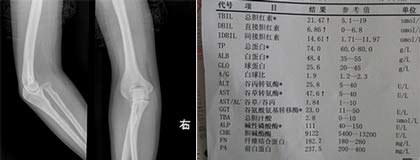

(图:刘先生入院后所做的CT检查及化验单)

入院检查:

体格检查:T38℃,R21次/分,P78次/分,BP110/80KPa,巩膜无黄染,浅表淋巴结不肿,无颈静脉充盈,双肺呼吸音清,心律齐,肘关节疼痛明显,下膝关节疼痛剧烈。

化验单:血沉21mm/h,类风湿因子59IU/ml,抗链球菌溶血素267/ml,超敏C反应蛋白18mg/L。